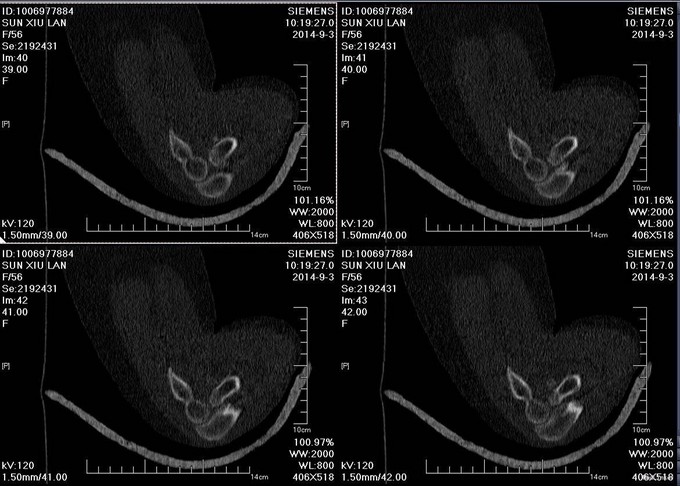

主诉:摔伤后右肘部疼痛10小时 患者自述2014-9-2 早8点自己走路时不小心摔倒,右肘部着地,导致右肘部疼痛、肿胀、活动受限,于当地医院拍片诊断为“右肘关节脱位”,给予手法复位, 为求进一步治疗来我院,诊断为“左肘关节骨折”,并收入我科,患者自受伤以来,无发热,无呼吸困难,无腹痛腹泻,饮食睡眠正常,大小便未见异常。

患者步入病房,左肘关节肿胀明显,压痛(+),骨擦音及骨擦感(+),左上肢感觉未见异常,左手指活动正常,左桡动脉搏动可触及。

患者入院后左肘关节石膏固定,左肘关节对症消肿等治疗。1周后完善检查后查无明显手术禁忌症后行左桡骨小头骨折切开复位内固定术。